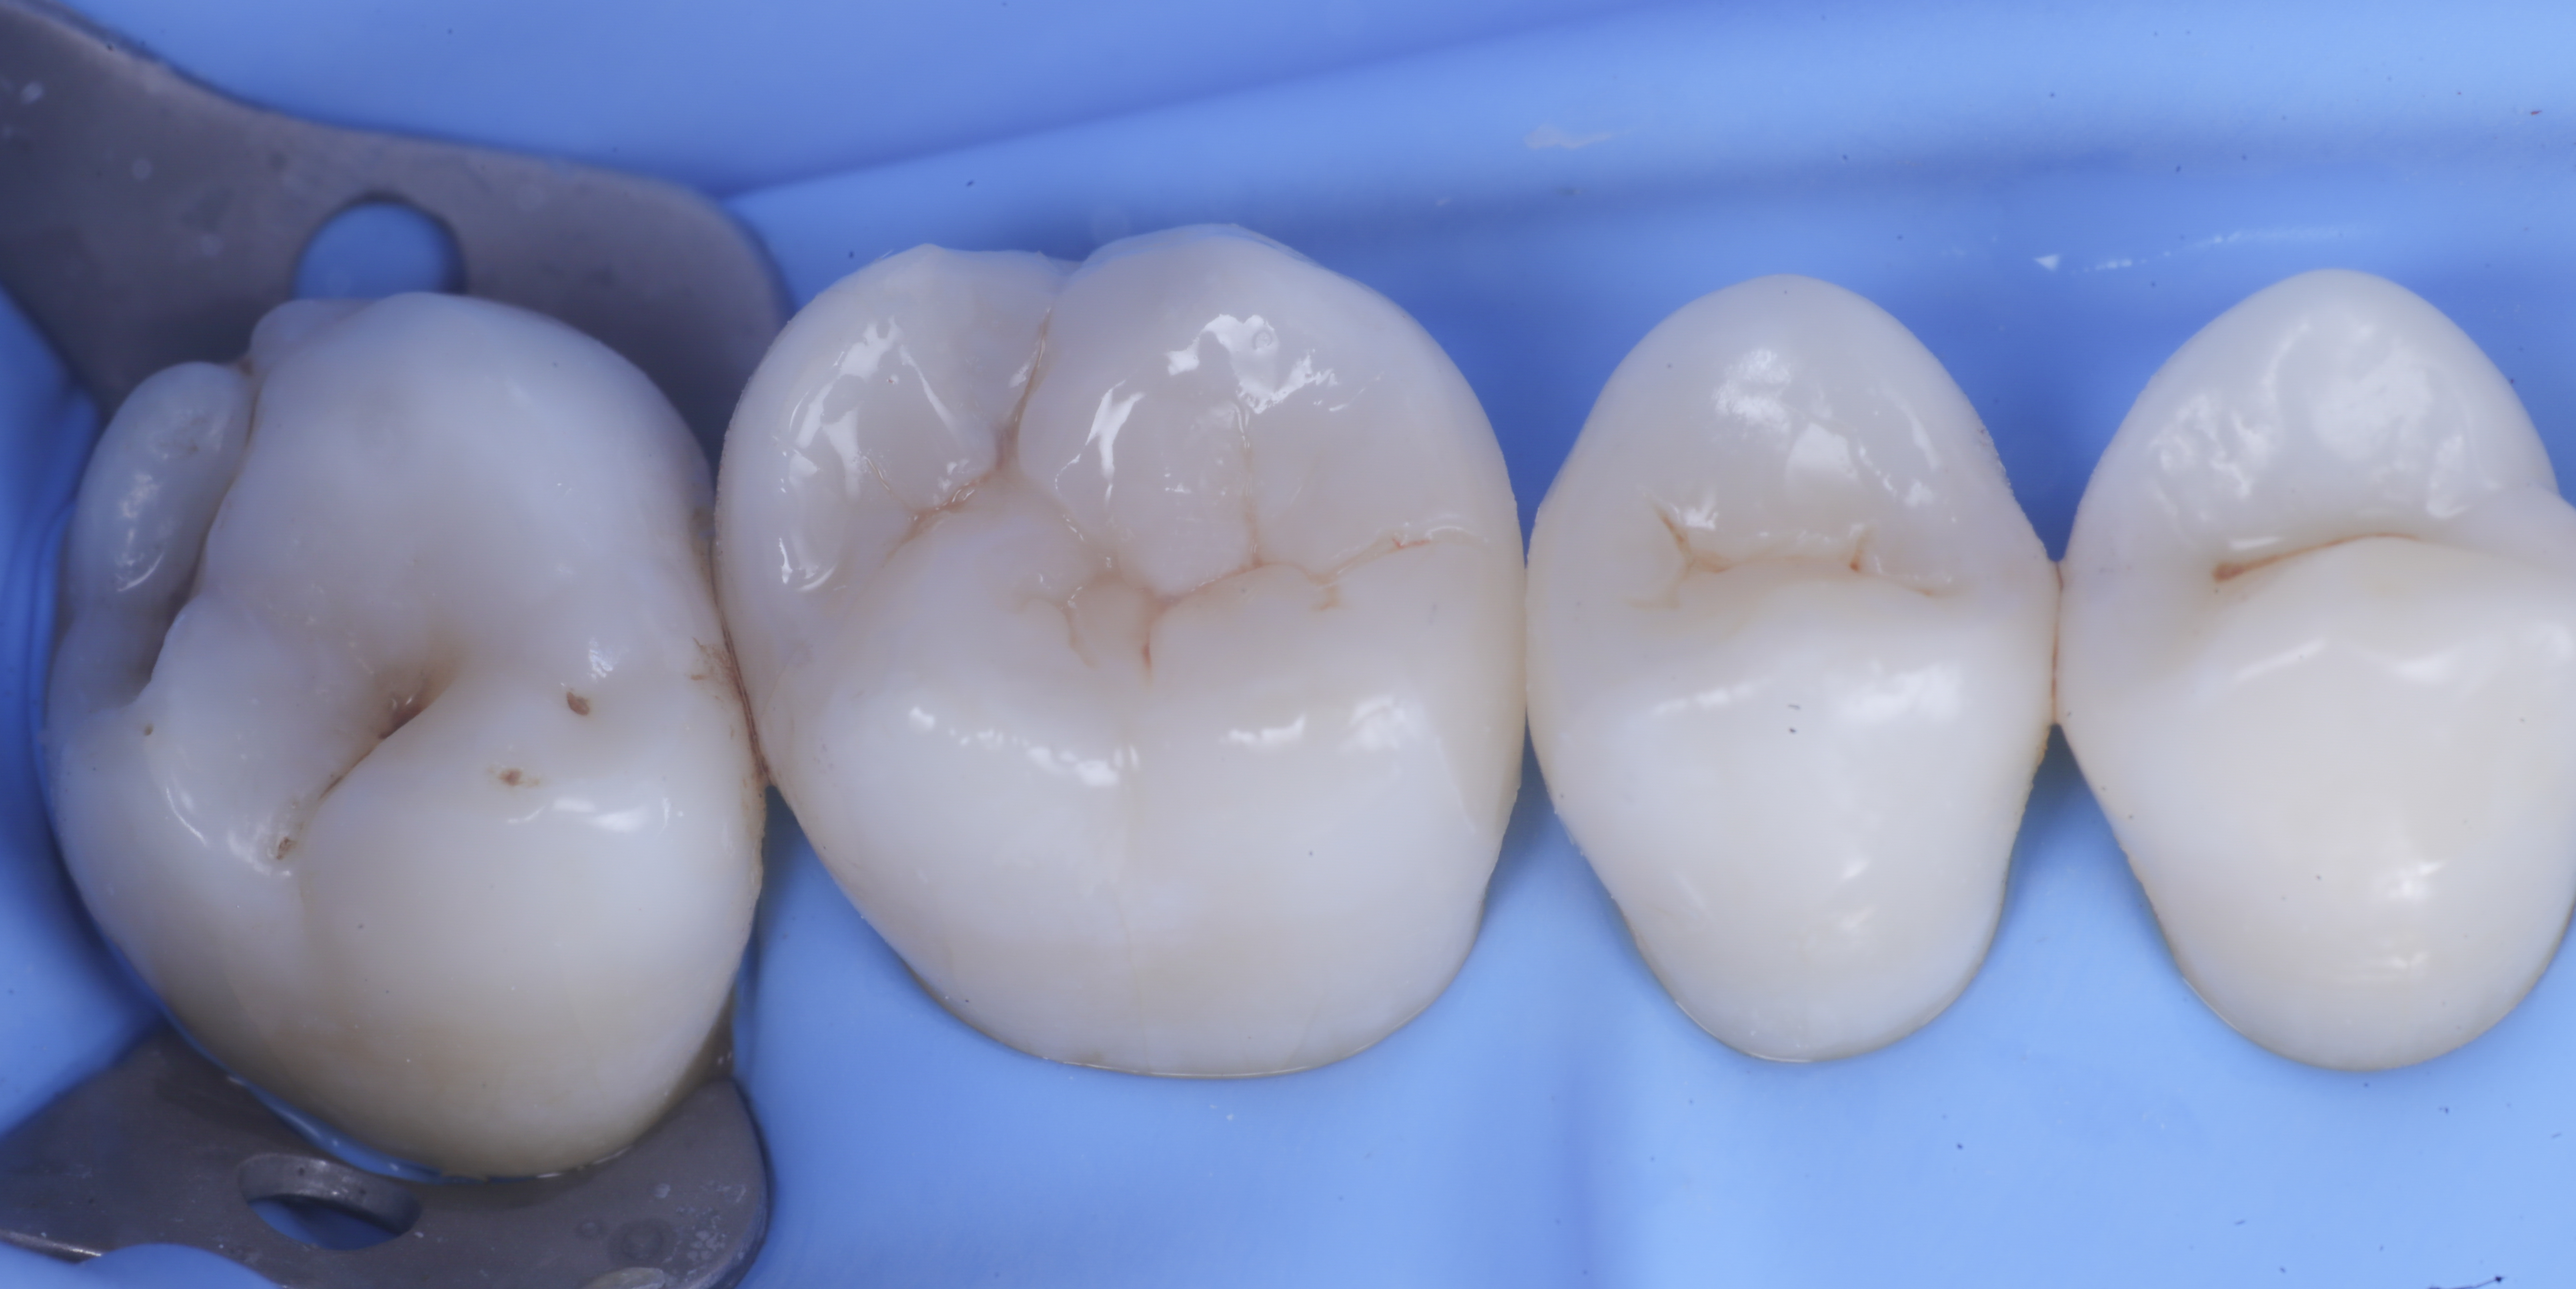

Trasformate le cavita da II classi a I classi si procede con la classica modellazione cuspide per cuspide, sfruttando le caratteristiche meccaniche e anche estetiche dei materiali compositi bulk.

foto 8 Modellazione ed aspetto occlusale

foto 9 Modellazione ed aspetto vestibolare

foto 10 Modellazione ed aspetto palatino